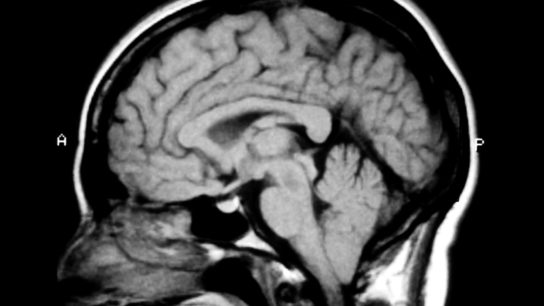

Determinations of brain death are becoming increasingly clouded by special circumstances, religious beliefs, and inconsistencies across state lines.